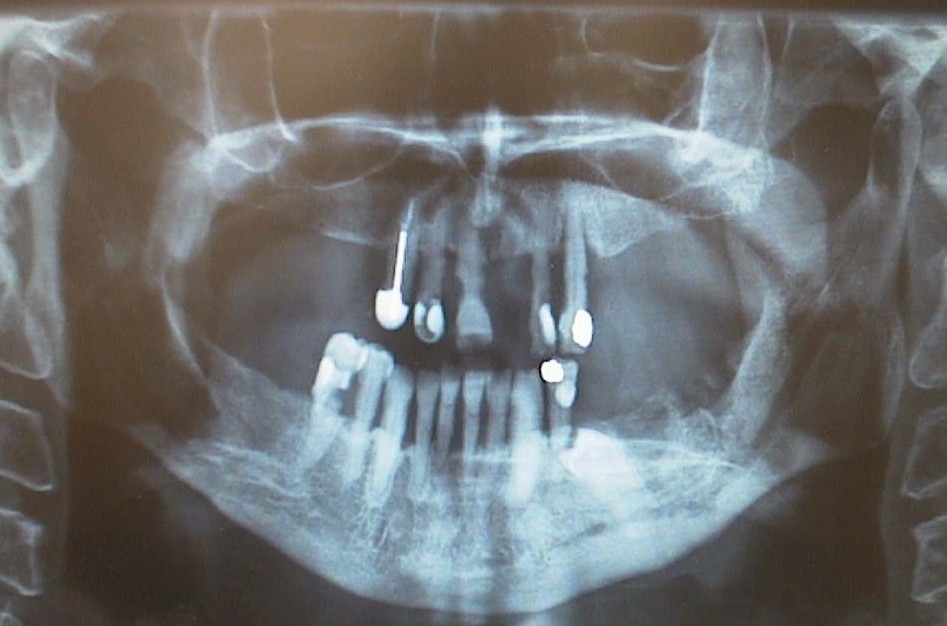

“I have lost a few teeth in my adult life,” Mr Bloomfield says.

“I’d go in and see the dentist and they’ll just pull the tooth out. It’s all that they’ll ever really do, they wouldn’t do anything else.”

When those patients eventually reach Dr Lim, they need on average 10 to 15 teeth removed, an outcome that in itself creates severe disability.